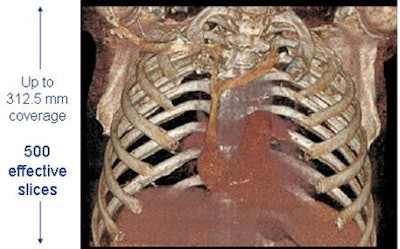

Higher slice counts and dual x-ray tubes do a good job of freezing motion and increasing coverage area, respectively, but the images aren't much sharper than the 16-slice data that's been available for a decade and, therefore, don't help much with noncardiac applications, Smith said. "That brought us into the direction of image quality and into the gemstone area," he said.

Still, for the "98% of imaging applications" that are noncardiac, qualities other than speed and coverage are paramount, and CT750 HD tackles image-quality issues that had not been addressed previously, Smith said. Documents provided to AuntMinnie.com showed gains in both spatial resolution and dose.

According to claims GE said were included in the system's 510(k) application, CT750 HD delivers spatial resolution of 230 microns at the 2-mm scan length, compared to approximately 300 microns for current-production 64-slice scanners. That translates to as much as 33% better resolution in body imaging for the new machine, up to 47% improved resolution in heart imaging, and up to 40% better low-contrast detectability -- all at up to 50% less dose in body imaging.